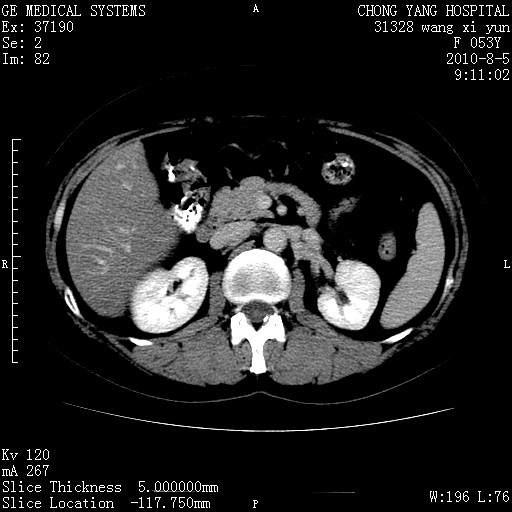

标题: CT28214:F41Y 血尿二十天,建议盆腔平扫加增强。

胆管细胞ca?

1)考虑肝左叶胆管细胞癌。2)脂肪肝。

支持胆管细胞ca。